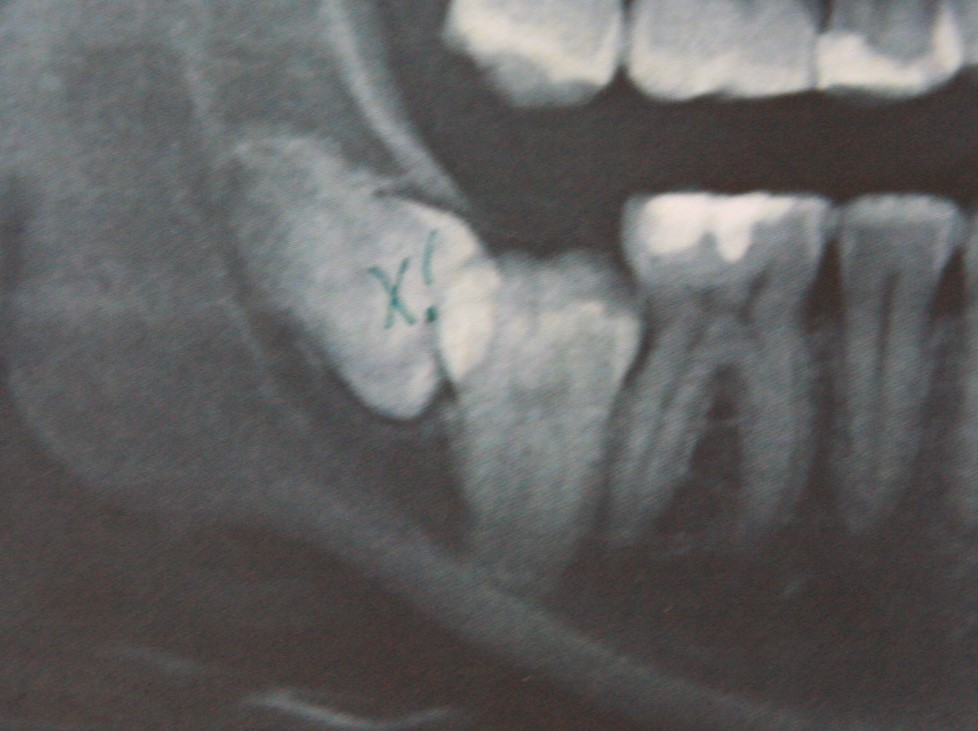

Делаем контрольный снимок, чтобы убедиться в том, что мы не повредили семерку:

И все. Вся эта работа заняла, максимум, 15 минут. Если кто-то в этом сомневается, есть два варианта проверить: